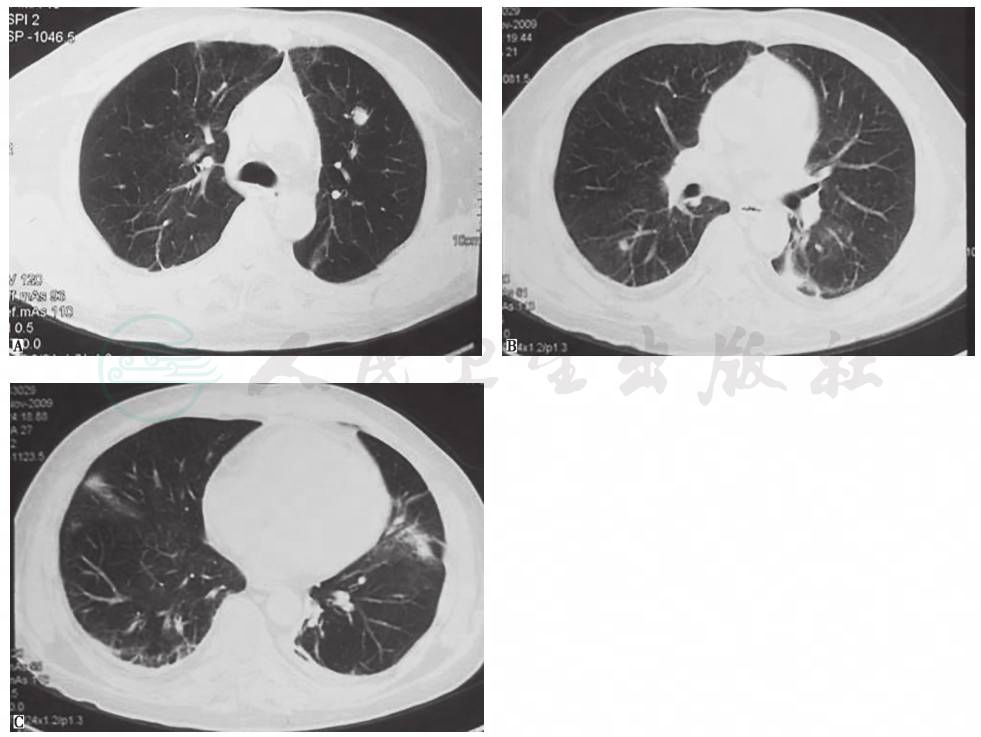

系列胸部影像学检查表现见图1~图5。

图3 胸部CT表现(2009-11-09)

胸部CT示双肺散在小结节、斑片影,双侧少量胸腔积液

图5 胸部CT表现(2009-11-19)

胸部CT示双肺多发结节、空洞影

3.胸部影像学特点为病初见左下肺斑片影,莫西沙星治疗后肺部阴影吸收,停用后肺部阴影短期内再次增多。

患者此次为急性起病,病初为中-高热,莫西沙星短期治疗一度有效,病情(临床表现和肺部阴影)得以缓解,但停药后短期内再次发热、肺部阴影再现(绝大多数肺部阴影在原有病变基础上增大),首先考虑为感染性疾病所致的可能性大,并且结合莫西沙星的治疗作用,考虑为莫西沙星能覆盖/部分覆盖的病原体(包括多种常见可导致社区获得性肺炎的病原体,如肺炎链球菌、苯唑西林敏感金黄色葡萄球菌、支原体、军团菌等)。鉴于患者病情加重后,胸部CT表现为在原来病变基础上出现结节、空洞,重点考虑金葡菌感染的可能,同时须鉴别由于库欣综合征、继发性糖尿病血糖水平控制差,其他多种病原(如结核分枝杆菌、非结核分枝杆菌、诺卡菌等)导致的机会感染,尚需进一步病原学检查结果证实。其次,还需要考虑非感染性疾病,尤其是肺部肿瘤性疾病。患者有库欣综合征,需要警惕神经内分泌肿瘤可能。由于患者肺部阴影在抗感染治疗后缩小,停药后在短期内又明显增大、增多,不是肿瘤性疾病常见的表现,故可排除。此外,虽然抗中性粒细胞胞质抗体(ANCA)相关性血管炎也可以表现为肺内多发结节、空洞影,但抗感染药物无效,与本病例病情变化情况不符。